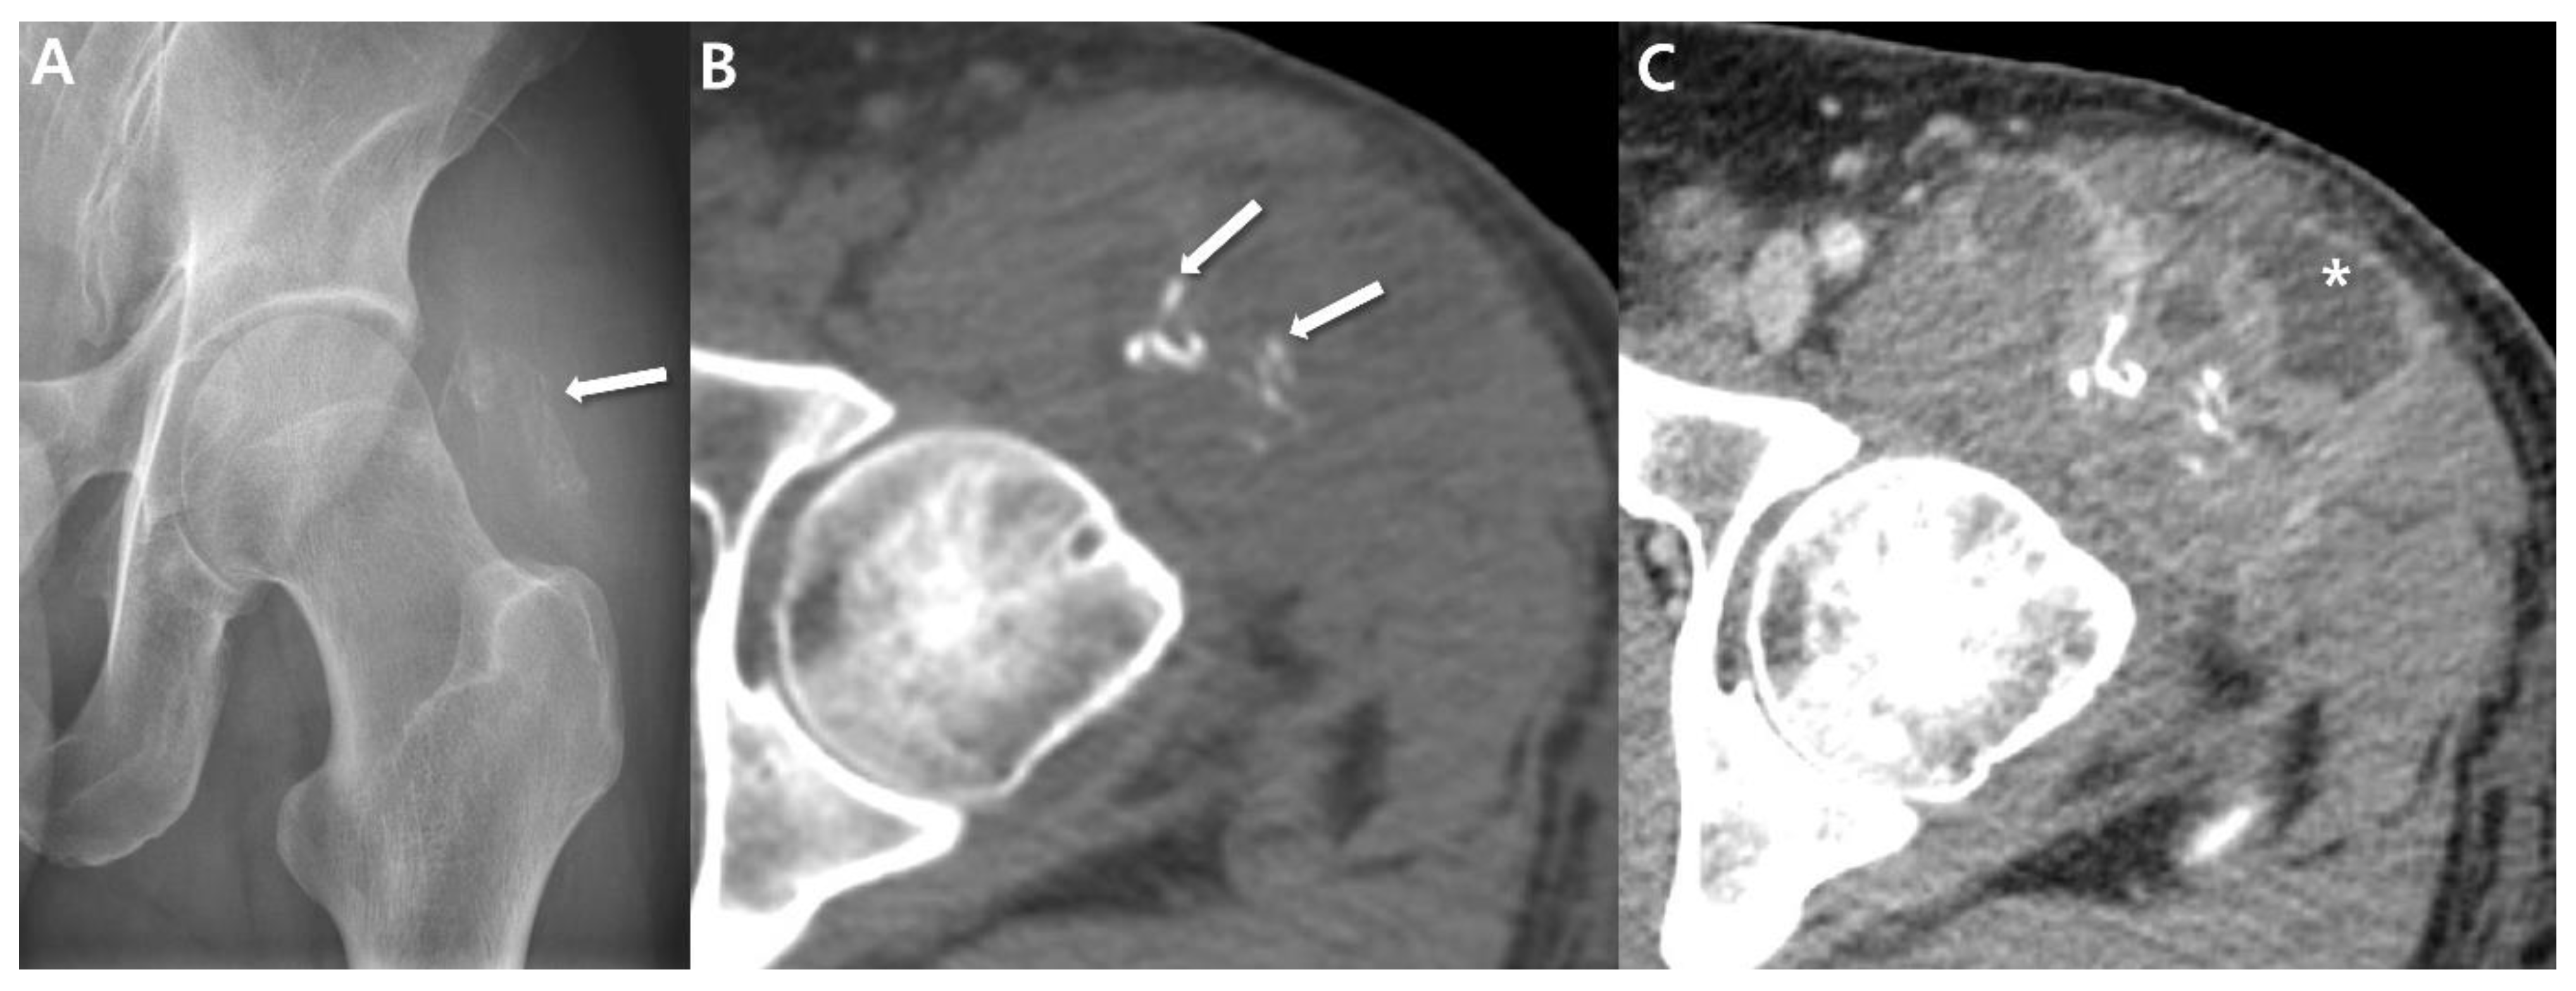

2.1. Radiographs

2.2. Computed Tomography (CT)

- Wilkerson, B.W.; Crim, J.R.; Hung, M.; Layfield, L.J. Characterization of synovial sarcoma calcification. AJR Am. J. Roentgenol. 2012, 199, W730–W734. [Google Scholar] [CrossRef]